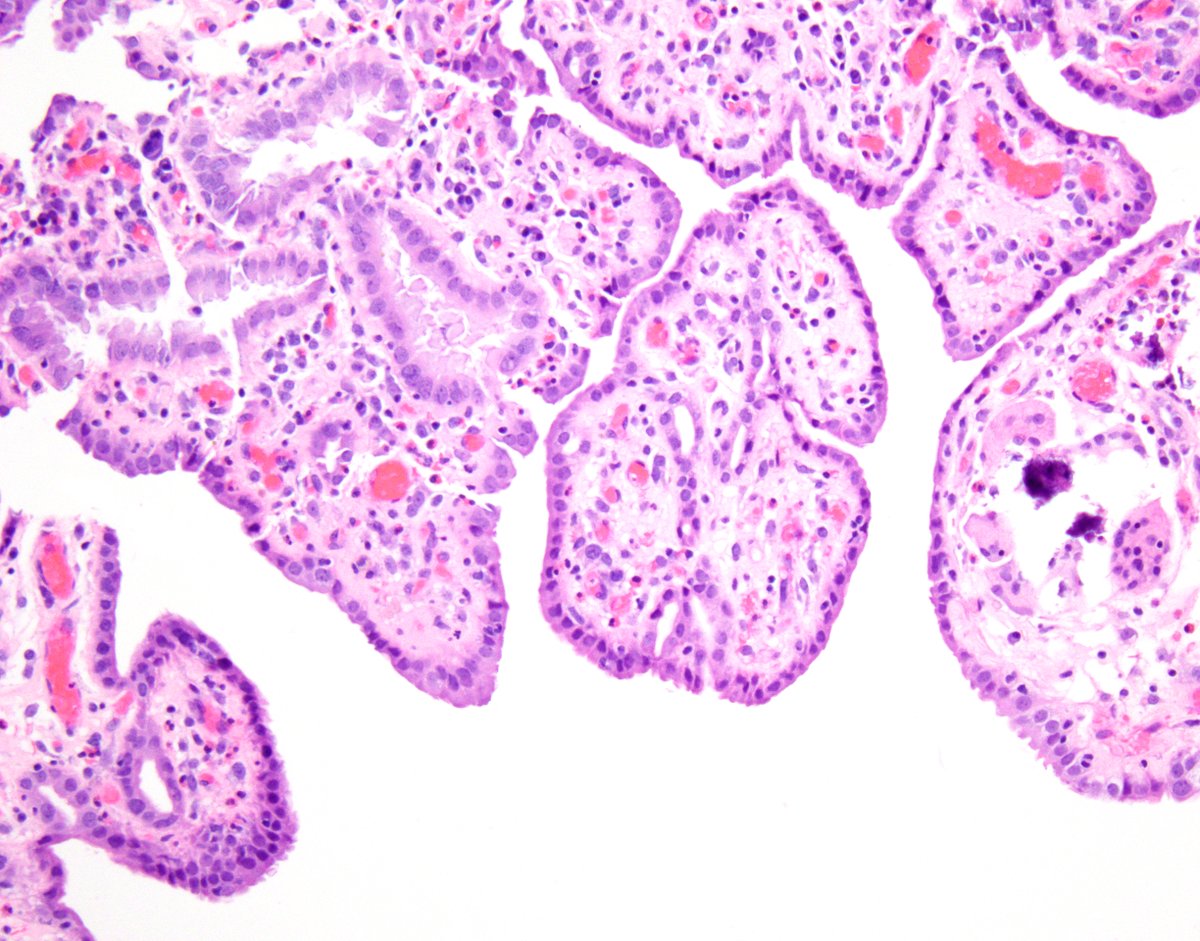

May is #bladdercancerawarenessmonth - important to recognize lesions which mimic #bladdercancer Nephrogenic metaplasia/adenoma: - various architectures (papillary, tubular/glandular, vascular-like...) - cuboidal to hobnail nuclear features - prominence of basement membrane

2

44

116